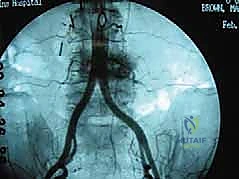

الخطوة 2: التعامل مع الأوعية الدموية (Vascular Mobilization)

هذه هي الخطوة الأكثر دقة. أمام العمود الفقري القطني توجد الأوعية الدموية الكبرى في الجسم (الشريان الأورطي والوريد الأجوف السفلي وتفرعاتهما). باستخدام أدوات دقيقة ورؤية مكبرة، يتم تحريك هذه الأوعية بلطف شديد لحمايتها وكشف القرص الفقري المستهدف (غالباً L4-L5 أو L5-S1).